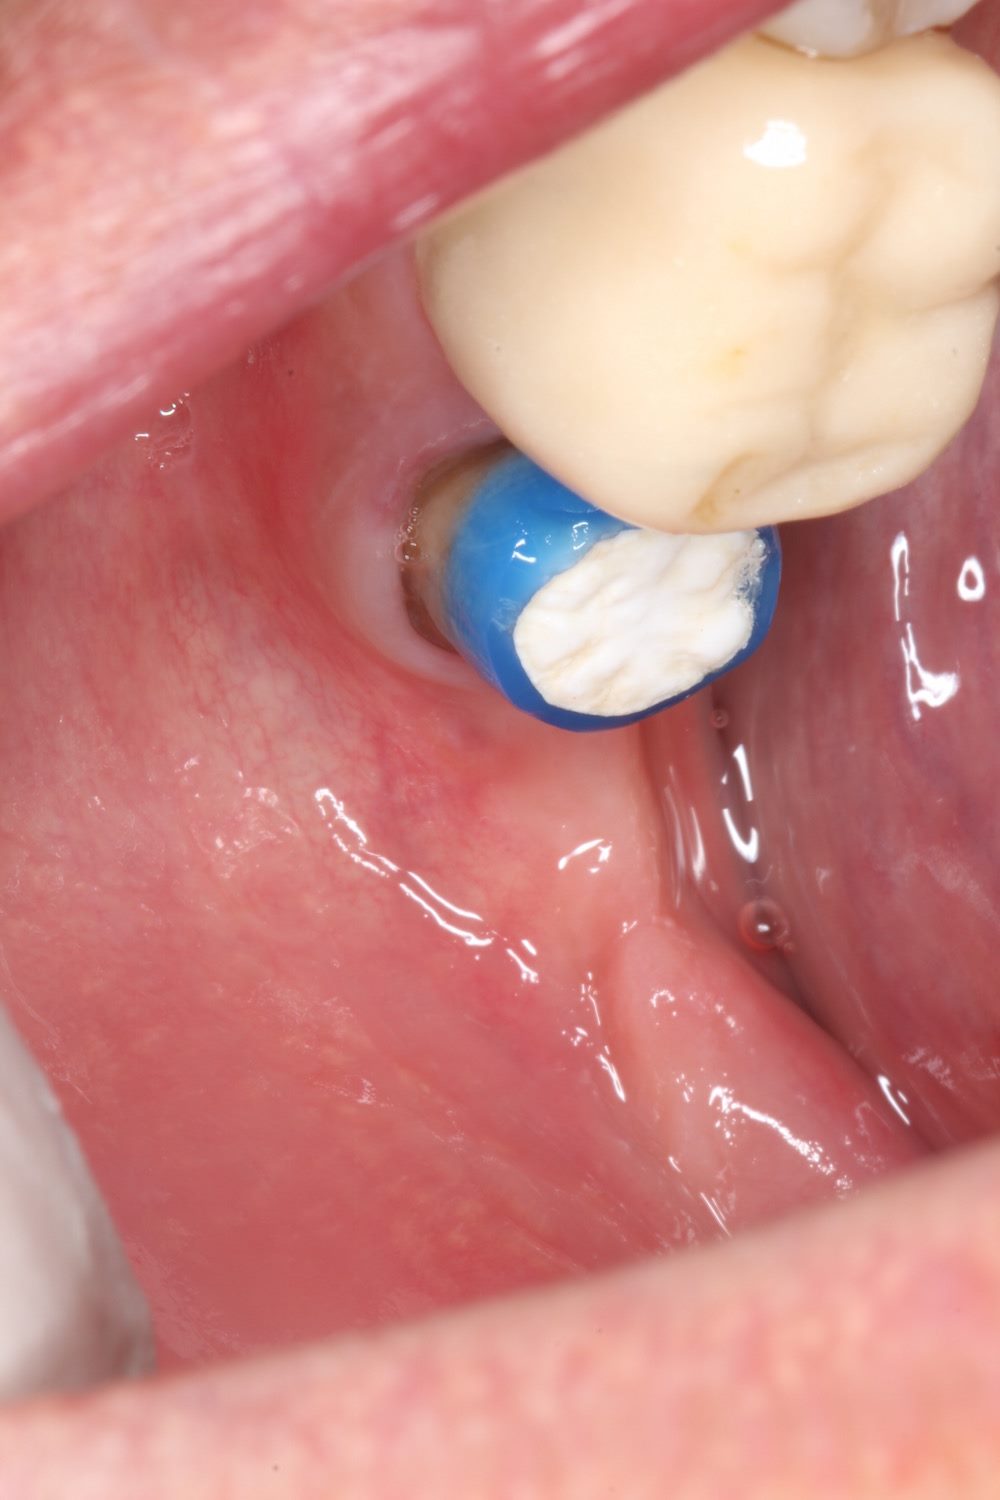

この炎症で、歯茎が腫れています。

来院時の状態です。術前にあった歯茎の腫れが引いています。感染が取り除けた証拠です。